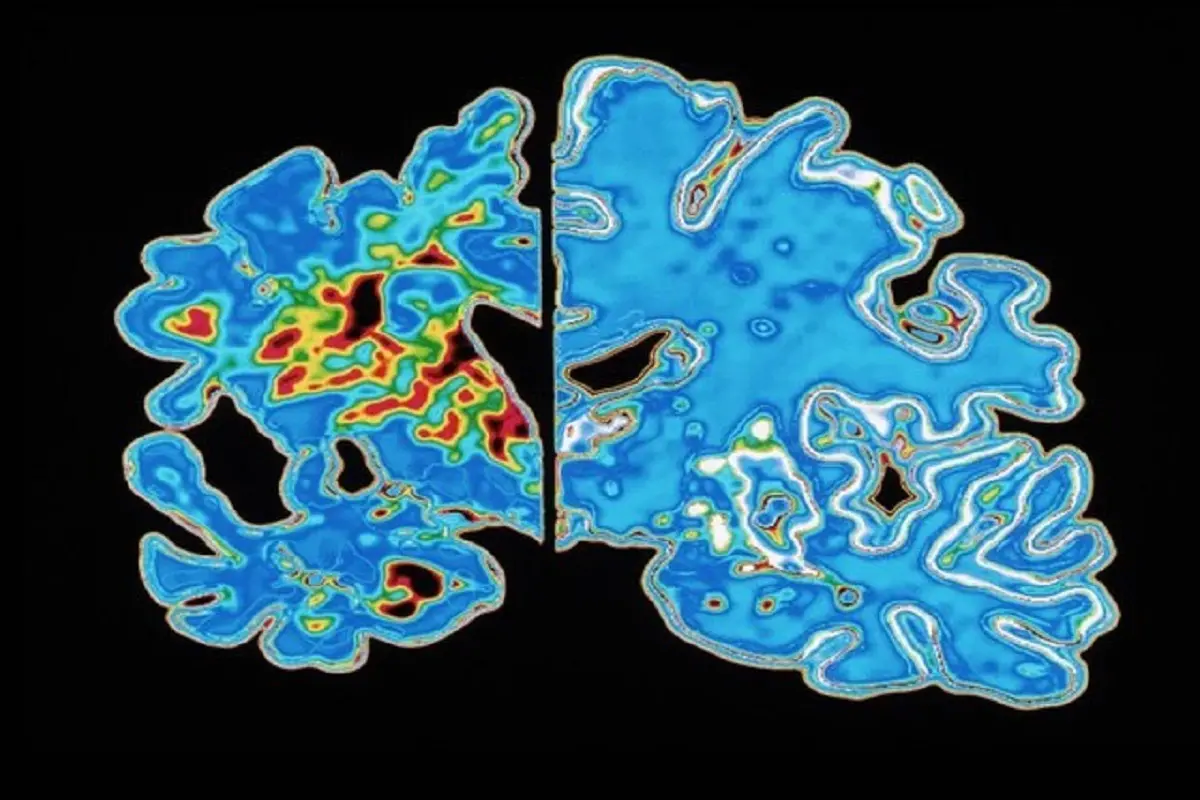

پروتئینهای تاو غیرطبیعی میتوانند رشتههای درهمتنیدهای تشکیل دهند که ارتباط میان سلولهای عصبی مغز را مختل میکند. آزمایشهای تصویربرداری مغزی که این تودههای درهم تنیده تاو را شناسایی میکنند، گاهی در تشخیص آلزایمر استفاده میشوند، و مطالعات اولیه نشان میدهد که چنین آزمایشهایی شاید بتوانند زمان بروز علائم آلزایمر را نیز پیشبینی کنند.

اما شیندلر میگوید این روشهای تصویربرداری دشوار و پرهزینه هستند. در همین حال، پژوهشگران در حال بررسی آزمایشهای سادهتر مبتنی بر خون هستند که میتوانند تاو را نیز ردیابی کنند.